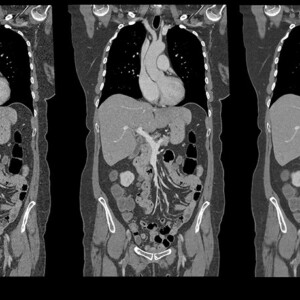

Στην εξέταση αυτή χρησιμοποιώντας ακτίνες Χ, σειρές ανιχνευτών και υπολογιστικά μηχανήματα παράγονται εικόνες (διατομές) εγκάρσιες και επιμήκεις της περιοχής του σώματος που εξετάζουμε.

Συμπαγή όργανα της ανώτερης κοιλιακής χώρας καθώς και άλλες δομές της απεικονίζονται με μεγάλη ακρίβεια με τη μέθοδο αυτή.

Παθήσεις και νεοπλάσματα ήπατος χοληφόρων, παγκρέτος, χοληδόχου κύστεως, σπλήνος, καθώς και των αγγείων της περιοχής διαγιγνώσκονται με την αξονική τομογραφία. Παθολογικές καταστάσεις του τμήματος του λεπτού και του παχέος εντέρου που απεικονίζονται δύναται να απεικονιστούν. Λόγω της ταχύτητας και της άνεσης για τον ασθενή χρησιμοποιείται για τη σταδιοποίηση όγκων καθώς και την παρακολούθηση τους.

Όργανα του ουρογεννητικού συστήματος, μέρος του εντερικού σωλήνα, η σκωληκοειδής απόφυση, αγγεία και μύες της κάτω κοιλίας απεικονίζονται με την μέθοδο αυτή. Συνέπεια αυτού η διάγνωση και παρακολούθηση φλεγμονών, λοιμώξεων, αποστημάτων, νεοπλασμάτων καθώς και απειλητικών για τη ζωή καταστάσεων όπως η περιτονίτιδα.